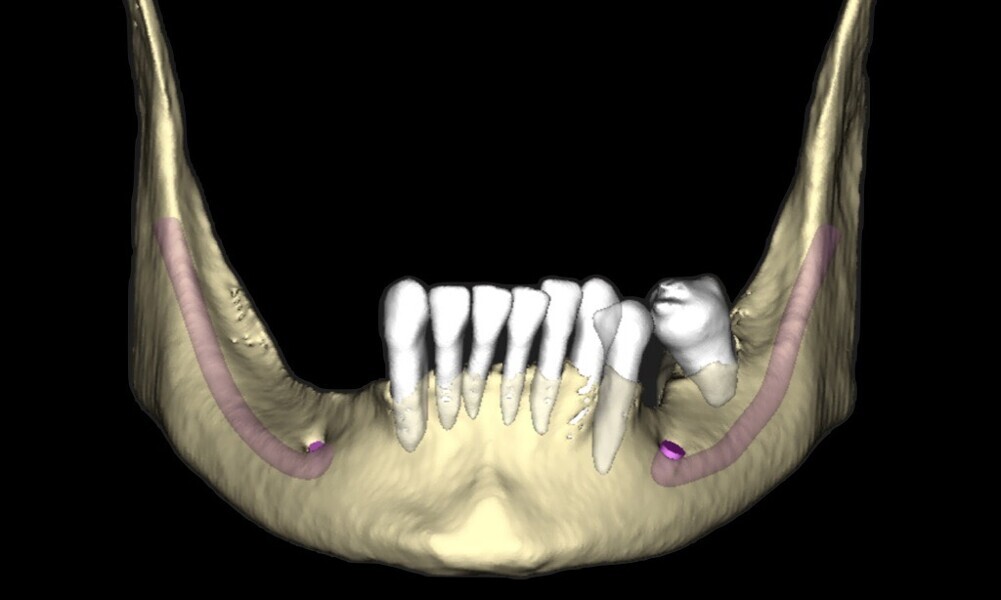

A CBCT scan was taken to determine the quality and quantity of the bone in the edentulous areas. The radiographic analysis showed adequate bone height in the areas of tooth extraction, allowing for immediate implant placement. The remaining bone provided sufficient support for initial stability during implant placement. Sufficient horizontal ridge width was observed in the potential implant sites, ensuring proper implant positioning without the need for additional ridge augmentation. Bone quality was favourable for immediate implant placement. The anterior maxilla presented moderate to good bone density (Type II–III) and the mandible excellent bone density (Type I–II), particularly in the posterior regions, indicating high primary stability for implants. Subsequently, digital impressions were obtained using the TRIOS intra-oral scanner (3Shape) and exported in STL file format (Figs. 8 & 9).

The remaining molars in the maxillary arch showed potential for preservation and function with regular periodontal therapy and careful monitoring. However, the other teeth were planned to be extracted owing to poor prognosis, primarily caused by advanced periodontitis and the associated severe bone loss (Fig. 10).

Fig. 10: Digital treatment planning was performed.

The patient presented with a hopeless dentition owing to periodontal disease, characterised by significant bone loss and tooth mobility. There were no clinical signs or symptoms of endodontic involvement or endodontic or periodontic lesions. However, several teeth were missing owing to previous extractions, and the remaining teeth showed signs of structural compromise. The presence of tooth mobility and retainers further indicated progressive periodontal tissue damage. No evidence of root fractures was observed clinically or radiographically. The clinical findings reflected the long-term effects of periodontal disease and emphasised the need for a comprehensive approach to restore function, aesthetics and oral health.